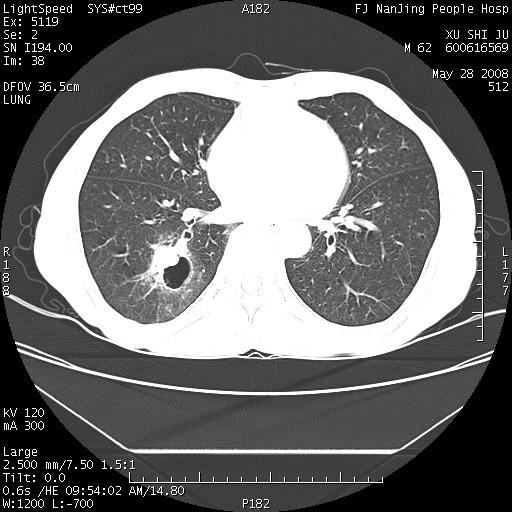

以下是引用杀毒软件在2008-5-28 19:16:00的发言:[br]病灶旁“晕轮征”,考虑肺真菌病

以下是引用qiushi在2008-5-28 20:01:00的发言:[br]空洞周围环状磨玻璃影(日晕征),考虑肺曲霉菌病.

以下是引用yuhongjun在2008-5-29 4:28:00的发言:[br]空洞周围环状磨玻璃影(日晕征),考虑肺曲霉菌病。支持! [br] [br]

以下是引用lrj在2008-5-28 21:10:00的发言:[br]所示应该是正常结构,是对称的,多个层面都有!也不像是内乳动脉或是肿大淋巴结![br]右下肺渗出性病变伴空洞形成,其洞内见一结节,以下诊断都有可能:1 右下肺曲菌感染, 2右下肺结核空洞形成伴曲菌感染!3右下肺结核空洞伴壁内占位形成,虽说后者发生的几率很低 但作为我们应该多考虑一下吧!最重要的结合临床